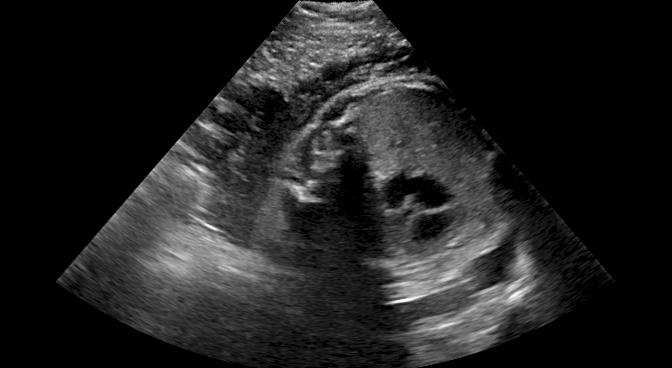

Fig. 6 compares the shadow confidence maps of the state-of-the-art methods and the proposed methods. RW and have the same parameters as used for Table I. The shadow confidence maps of the baseline, the proposed method and the proposedAG method are generated directly from input shadow images by confidence estimation networks. Overall, the proposed method and the proposedAG method achieve more visually reasonable shadow confidence estimation than the baseline and the state-of-the-art on different anatomical structures shown in Fig. 6. The proposed method and the proposedAG method are able to highlight multiple shadow regions while the RW algorithm shows limitations for most cases, especially for disjoint shadow regions.

Row I in Fig. 6 shows a fetal brain image from . The confidence estimation of shadow regions from the baseline, the proposed method and the proposedAG method are similarly accurate since we use fetal brain images to train the confidence estimation networks in these three methods. These outperform [16] and [22]. Rows (II-IV) in Fig. 6 show shadow confidence maps of non-brain anatomy from , including lips, abdominal and cardiac. The baseline failed on unseen data during inference. However, the proposed methods are able to generate accurate shadow confidence maps because of the generalized shadow features obtained by the shadow-seg module. Furthermore, the “Lips” example shows that our method is capable of detecting weaker shadow regions that have not been annotated in manual segmentation. This indicates that the confidence estimation network has learned general properties of shadow regions.